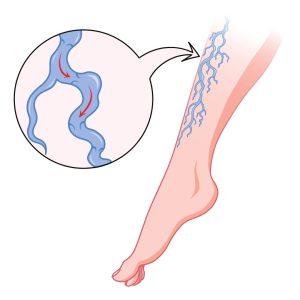

Varicose Veins

>>Therapies to improve circulation and reduce pain and swelling.